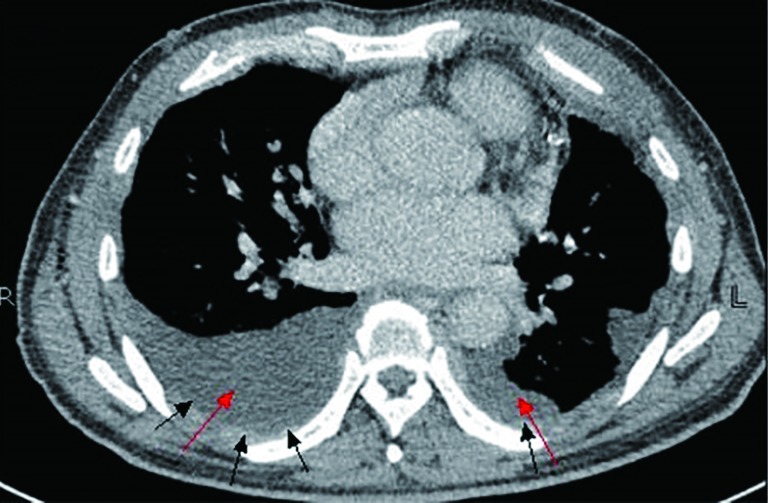

The bone marrow aspiration biopsy showed that hyperplasia of original plasma cells (1.5%) and active hyperplasia of naïve plasma cells (15.5%) (Figure 2). A thoracoscopic pleural biopsy of right side through video-assisted thoracic surgery was performed. Multiple nodules of pleural surface and partial lung collapse could be seen (Figure 3). The pathology of the specimen revealed abnormal proliferation of plasmocytes on hematoxylin and eosin (HE) stains. The immunohistochemistry test of the specimen showed: CD31 (+), CD34 (+), Ki67 (50%+), CD138 (+), CD38 (+), Kappa (+), Lambda (–), MUM1 (+) (Figure 4).

Figure 2.

Giemsa-staining of the bone marrow: Malignant plasma cells were detected in the bone marrow. The cells have large eccentrically placed and pleomorphic nucleis and prominent nucleolis (arrows) (Wright-Giemsa, ×1,000).